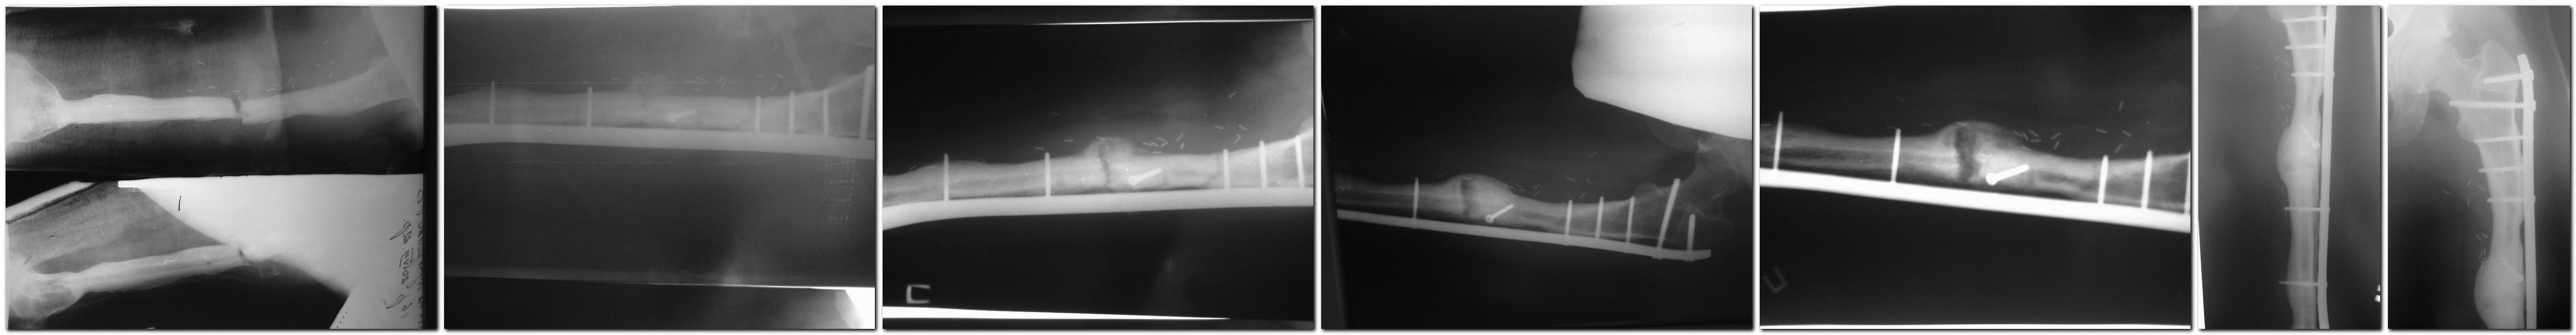

(девочка 19 лет, остеосаркома бедра 2010 г, лечение - резекция бедренной кости с замещением дефекта васкуляризованным малоберцевым аутотрансплантатом, МОС длинной L-oбразной 95 градусной пластиной, через год удаление импланта (консолидация концов трансплантат-бедро на фоне миграции винтов). 2012 год -перелом малоберцевого трансплантата, синтез индивидуально изготовленной пластиной с угловой стабильностью. В последующем признаки резорбции в зоне перелома. Возникал вопрос про рецидив саркомы, нестабильность синтеза,и соответственно тактику ведения больной. Больная и родственники категорически отказывались от проведения биопсии. Тогда выбрал выжидательную тактику, лечение - курс пролиа (Деносумаб). Снимки в хронологичной последовательности, интервал 2-3 мес. На данный момент жалоб нет, полная функция.